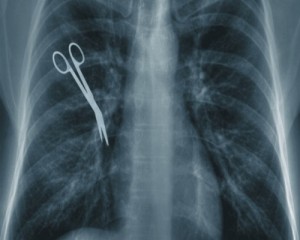

Is It Worth it to File a Malpractice Claim?